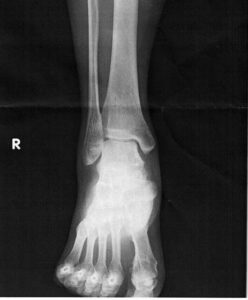

腓骨疲労骨折

腓骨疲労骨折は、ランニングやジャンプなどの繰り返しの負荷が腓骨に加わることによって引き起こされる骨折です。脛骨疲労骨折と同様に跳躍型と疾走型に分けられています。 跳躍型は近位1/3、疾走型は遠位1/3に好発するといわれ […]